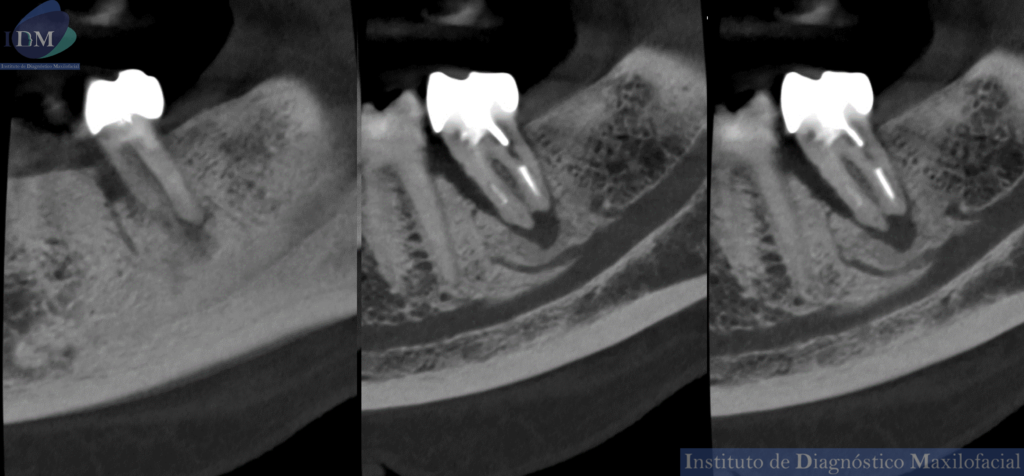

Así mismo se evidencia en la tomografía localizada una variante anatómica por parte del conducto dentario inferior. Donde se visualizada dos ramos accesorios del tronco principal sin confluencia.

CORTES TANGENCIALES